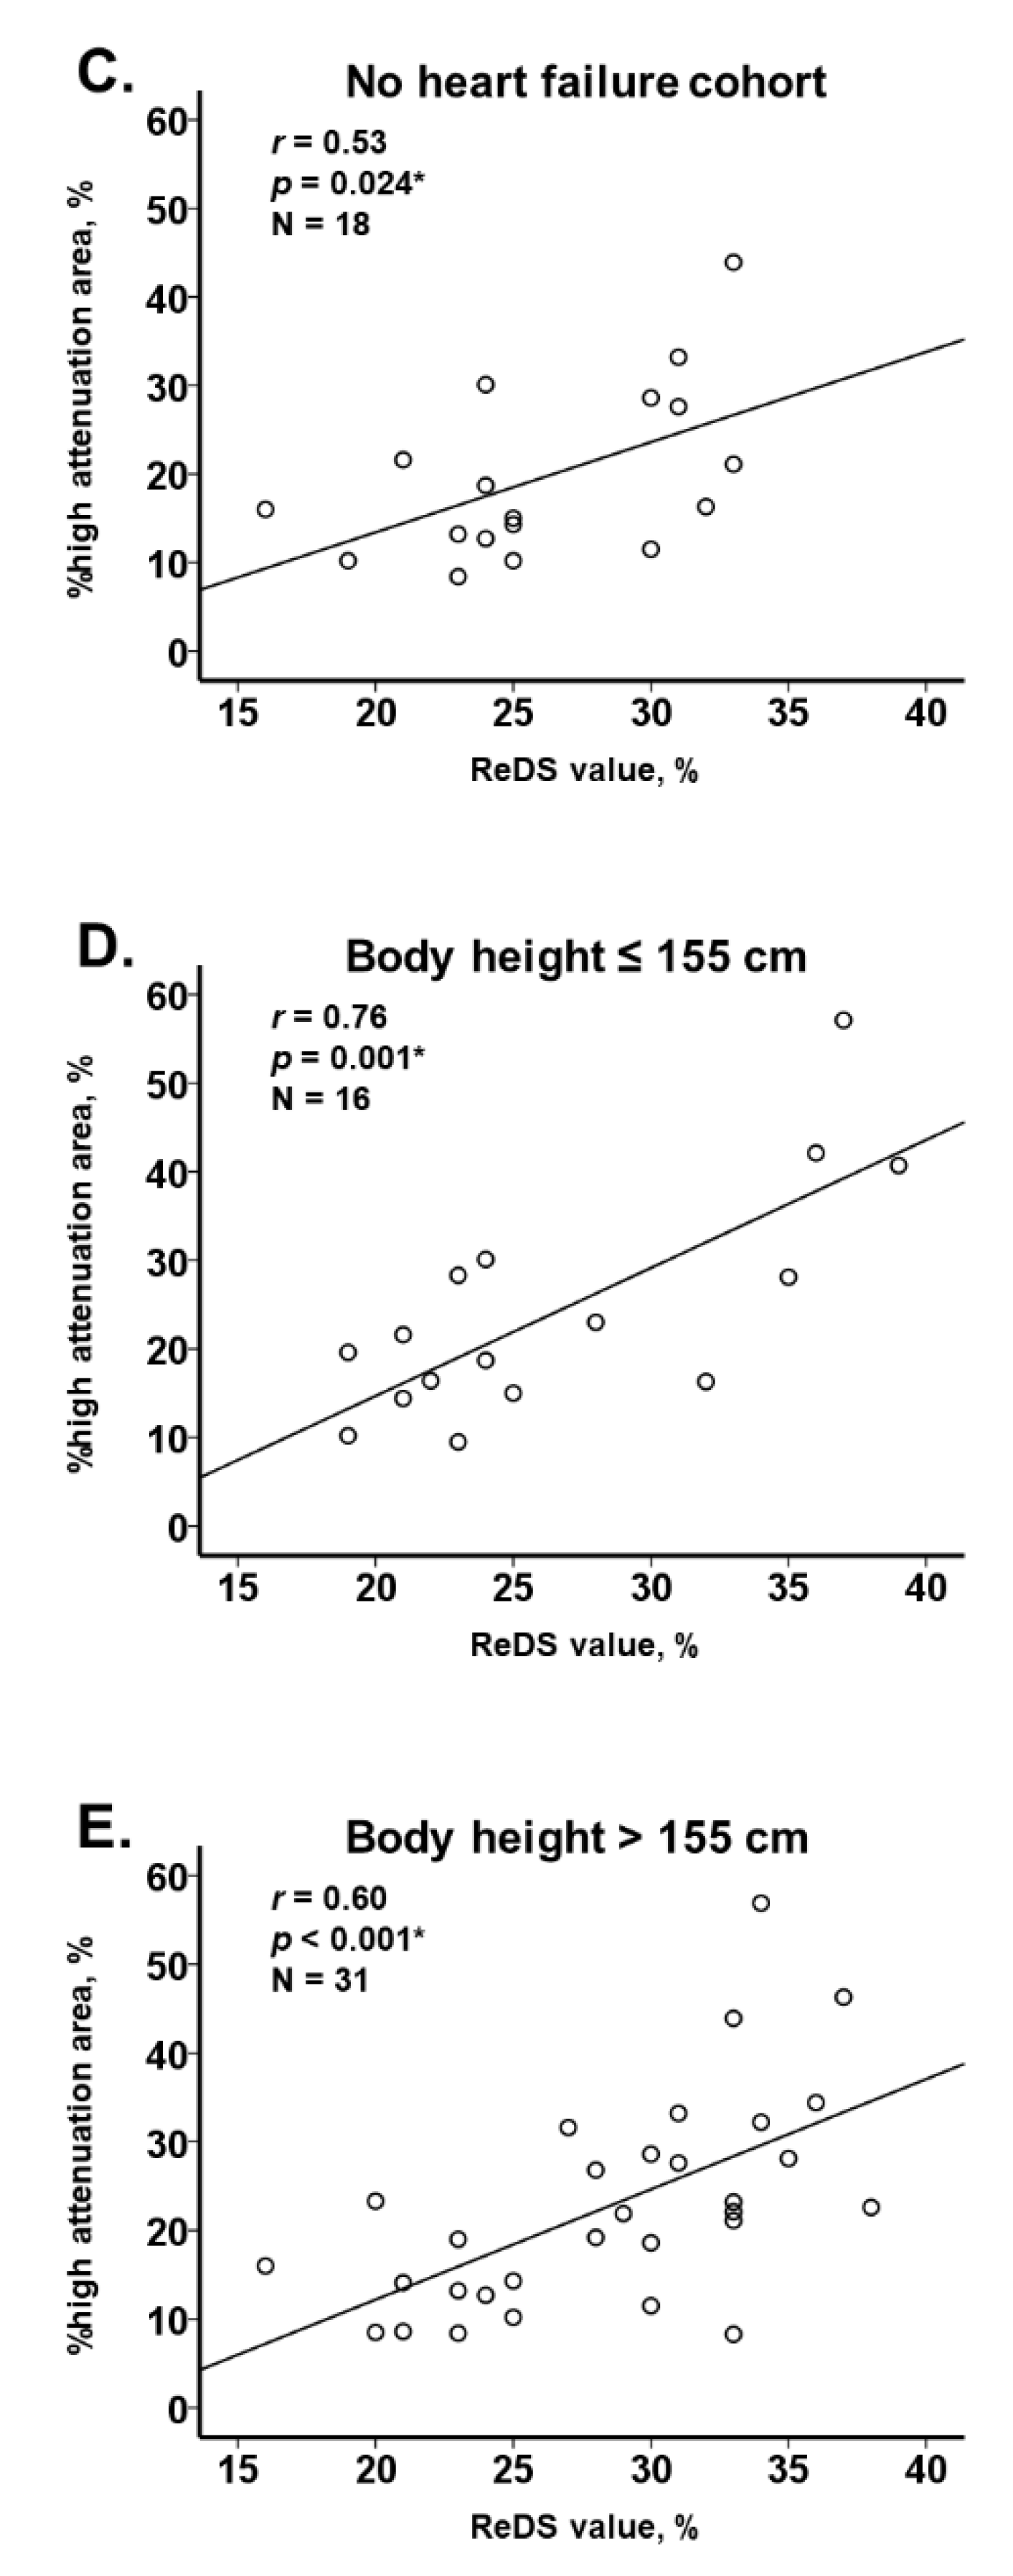

3.2. ReDS Value and %High Attenuation Area